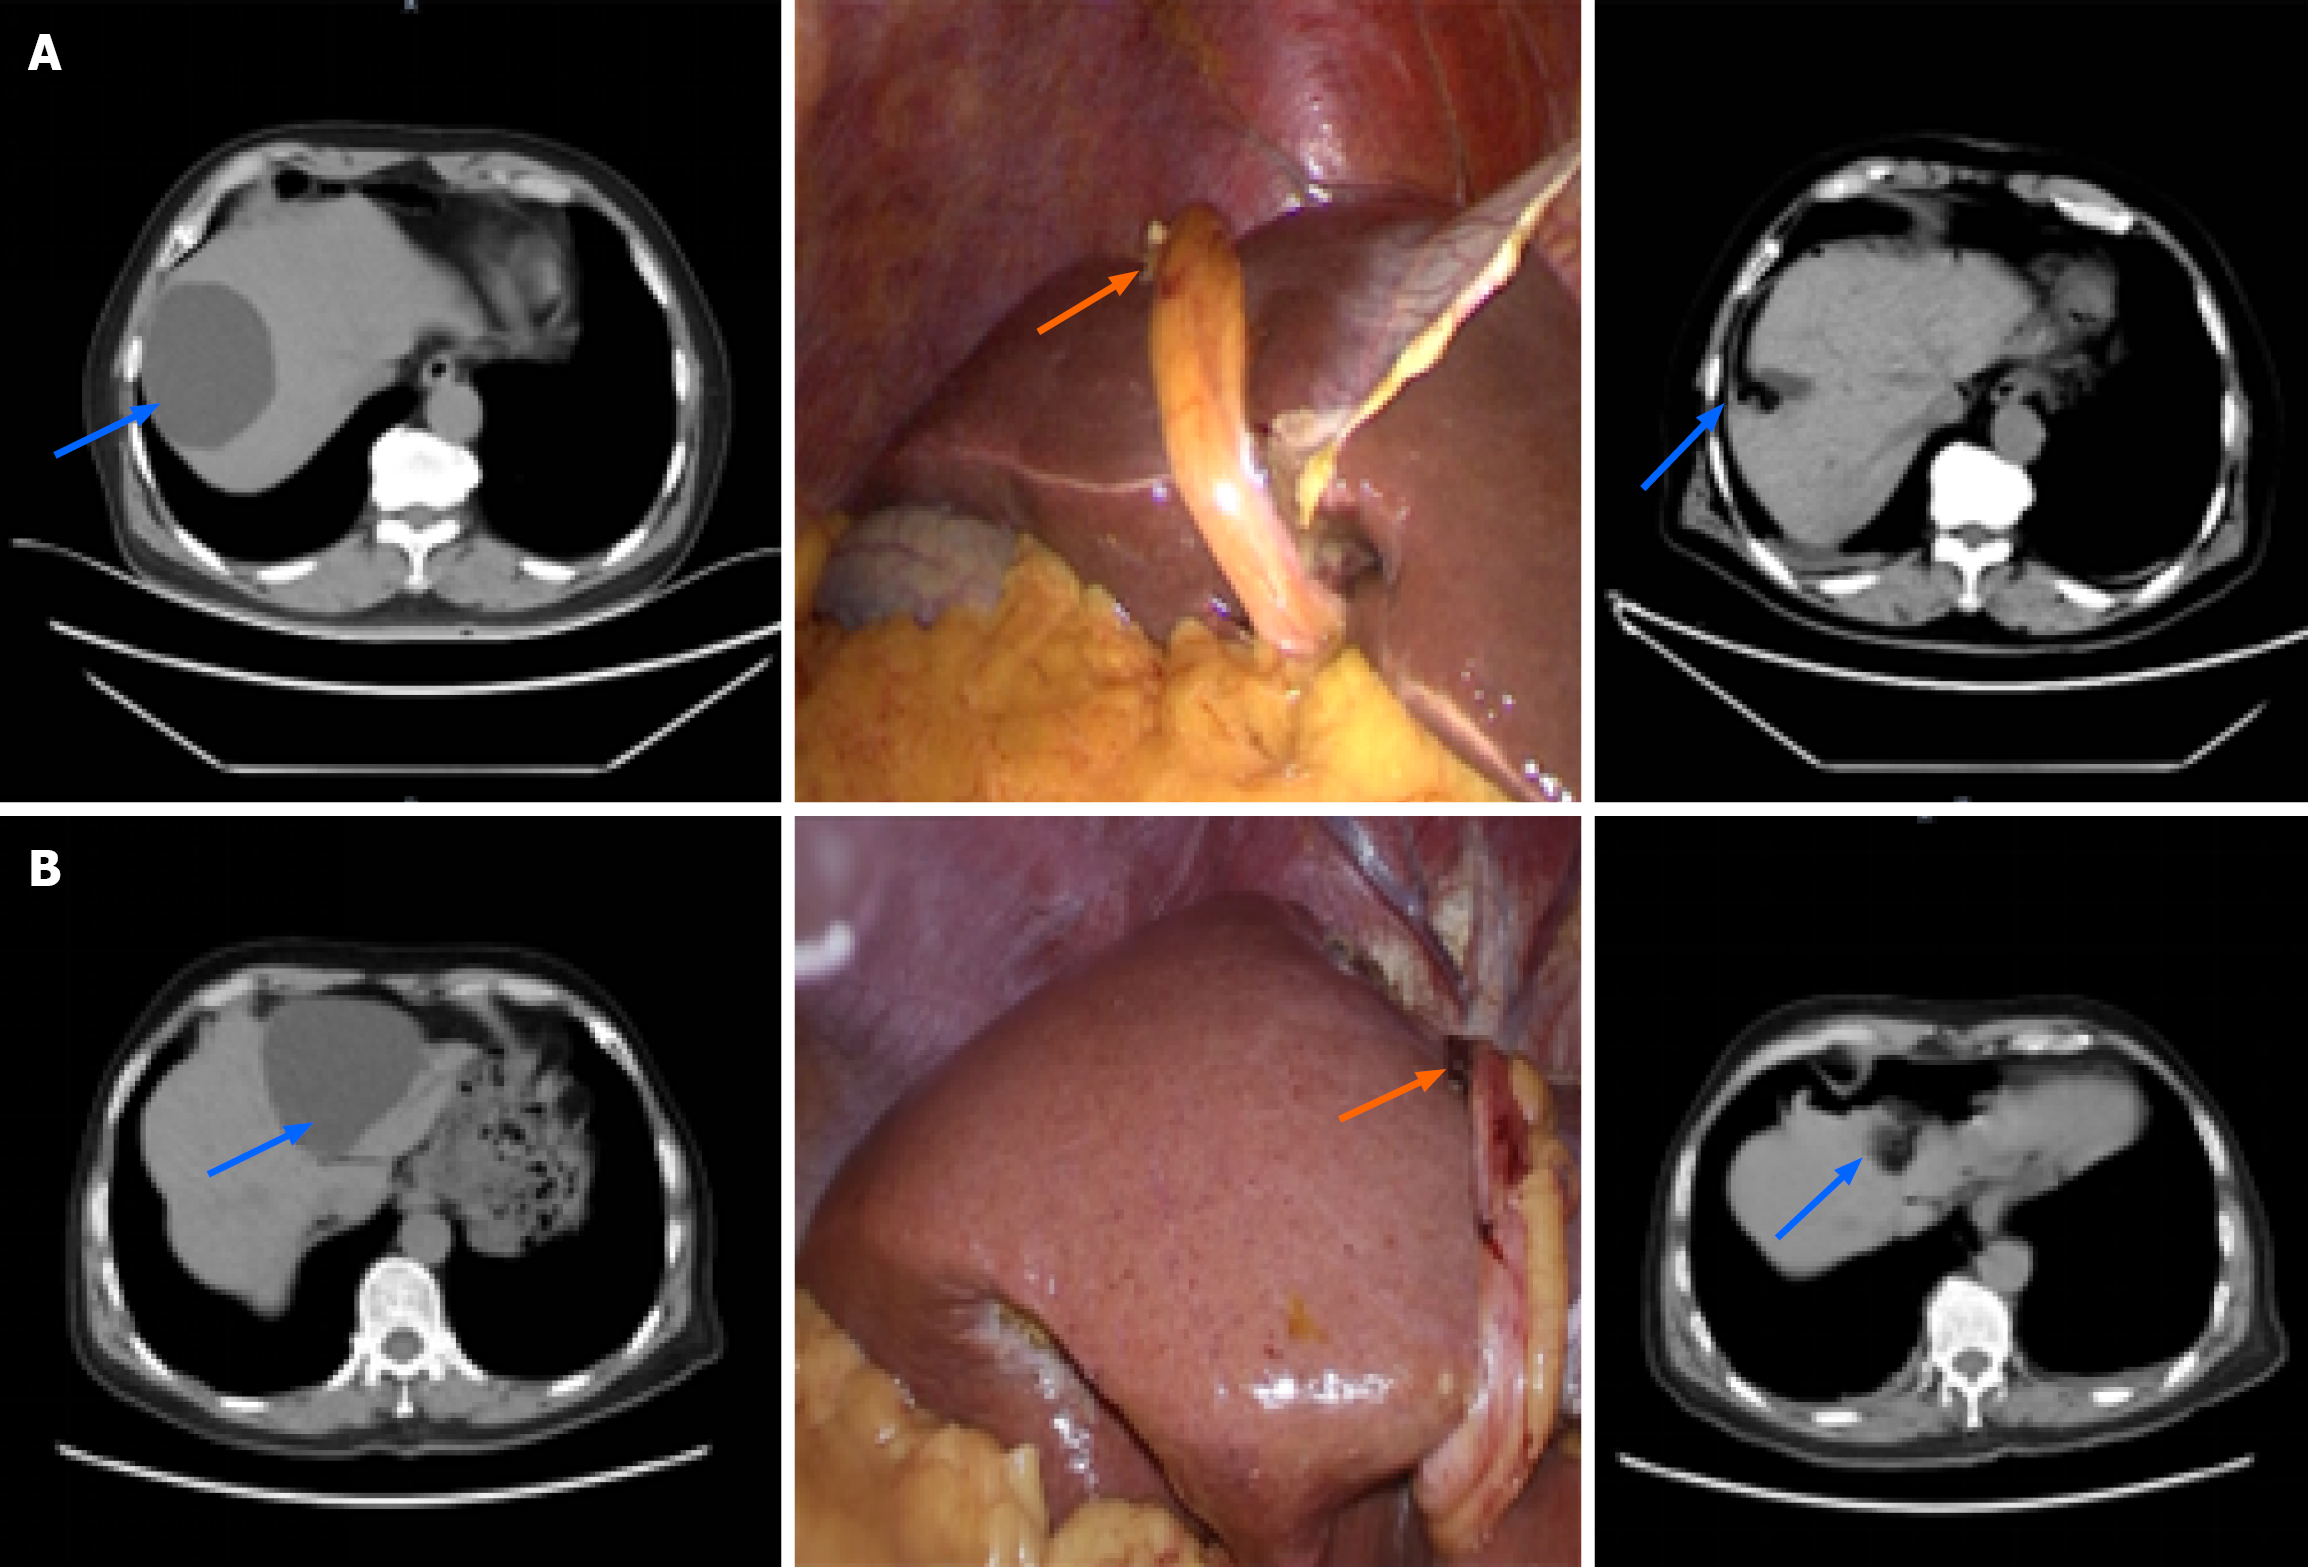

Figure 1 Hepatic cyst.

A: A case of a right hepatic cyst. The blue arrow traces the preoperative and one-year postoperative appearance of the hepatic cyst as visualized on computed tomography scans, demonstrating the significant change following surgical intervention. The orange arrow directs attention to the round ligament of the liver, which has been meticulously sutured and anchored to the base of the cyst; B: A case of a left hepatic cyst. The blue arrow shows the preoperative and one-year postoperative computed tomography images, revealing the effective management of the cyst. The orange arrow highlights the round ligament of the liver, which has been skillfully sutured and fixed in place.